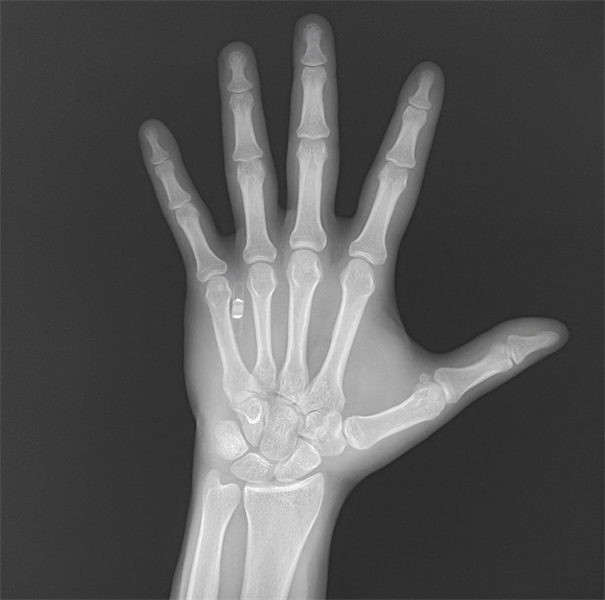

Le 25 avril, une entreprise britannique a présenté une puce qui peut être implantée dans la main. Une fois la puce implantée dans la main, un client peut réaliser le paiement de ses achats par un simple geste de main. Cette puce co?te 199 euros.

Selon le directeur exécutif de la société, la puce pèse moins d'un gramme et témoigne d'une compatibilité biologique, qui lui permet d'être implantée dans la main sans interagir avec les cellules du corps humain.